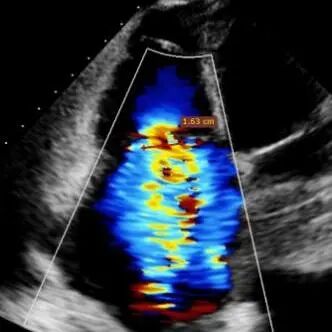

Echocardiographic findings indicated: Type IIIB quadrileaflet tricuspid malformation with extremely severe tricuspid regurgitation (5+, vena contracta: 16.1 mm on average). Regurgitant orifices were located at the anterior-septal, central, and posterior-septal regions, with a 11 mm central gap, leaflet tethering (tethering height: 10 mm), and tricuspid annular dilatation (mean annular diameter: 53 mm). The inferior vena cava diameter was approximately 25 mm, and RV FAC was 40%.

Baseline regurgitation after anesthesia

Postoperative regurgitation